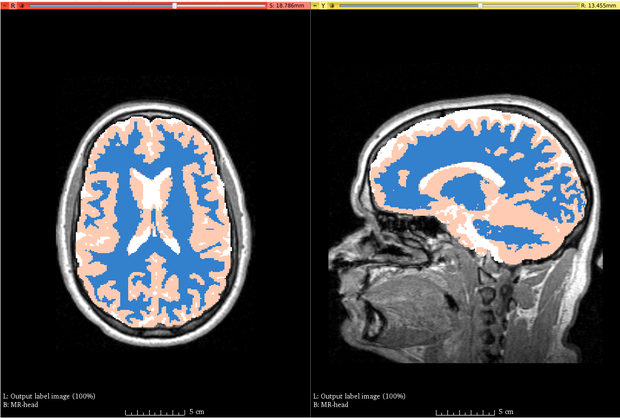

Example Output. Brain MRI segmented using ABC

The processing involved in the module can take up to five minutes for a typical MR image, using the default setting that was chosen to generate coarser results. Speed-ups are possible by increasing the number of threads (specified in the Speed panel). Results with higher accuracy can be obtained by increasing the maximum polynomial degree of the bias field (in the Advanced panel), increasing the number of pre-filtering iterations (in the Advanced panel), and switching to finer sampling for image registration (in the Speed panel).